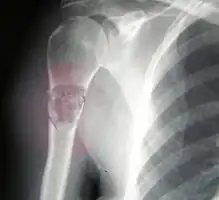

Telangiectactic osteosarcoma of the humerus

- Telangiectatic OS